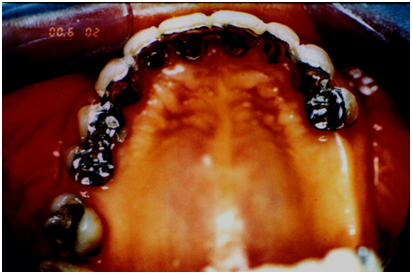

A 43-year-old woman having 22 teeth and destructed bone and supporting tissues, applied for dental treatment (Figure 1). After completion of her periodontal and orthodontic therapy, arch splinting via adhesive partial crown construction were done at the first step of the prosthodontics (Figures 2 & 3). Then a flexible gingival epithesis was constructed for esthetic and phonetic requirements, by a one-component silicone material (Gingivamollâ Detax GmbH & Co.KG, Ettlingen, Germany) which was produced according to the clinical and laboratory technique described by Iselin et al. [4] (Figure 4). Speech records were taken before and after the epithesis insertion, in a standard position where the distance between the 16 BIT stereo microphone and the patient was 40 cm’s in a sound proof room. Tests were performed in two steps, where sound characteristics were determined by the pronunciation of letter and text reading. During the speech tests, the letter sounds were classified according to their pronunciation specialties of basic articulations as sibilants, plosives, fricatives, liquids, glides and nasals which were previously defined by Burnett [5].

Figure 1: A case showing advanced destruction of periodontal tissues that caused phonetic voice disorders.